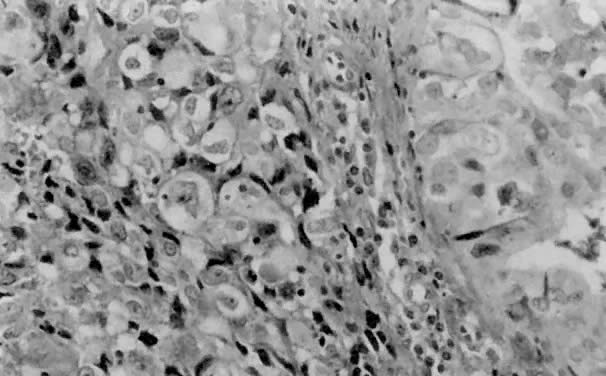

Clear cell carcinoma accounts for about 1% to 5% of endometrial carcinomas in most reports. It is associated with a poor prognosis (5-year survival rate of about 35%)20,46 and occurs almost exclusively in postmenopausal women. Although there are no distinctive macroscopic features, there are four histologic growth patterns that may aid in the diagnosis. These patterns are, in decreasing frequency, papillary (Fig. 13), tubulocystic, glandular, and solid (Fig. 14). Clear cell, hobnail, and cuboidal are the three cell types one may encounter. Most neoplasms display two or more patterns, as well as a mixture of cell types. Because of abundant glycogen accumulation, the cytoplasm of the neoplastic cells usually appears clear histologically, although it may be eosinophilic. The nuclear changes are also distinct, with irregular nuclear outlines and chromatin clumping, especially along the nuclear envelope.49 Nucleoli often are large and may be multiple. The nuclei of hobnail cells protrude into cystic spaces in the papillary variant (see Fig. 13). FIGO grading is restricted to nuclear grade in clear cell carcinoma (which is almost exclusively grade 3).22 In addition to the high nuclear grade, these patients tend to present with high-stage disease, thus contributing to their poor prognosis.

Fig. 13. ( A) This example of the papillary pattern of clear cell carcinoma demonstrates complex papillae with fibrovascular cores lined by one to multiple layers of clear cells. ( B) Hobnail cells protrude into a cystic space ( arrow ). Other cells display the typical clear cell morphology with irregular, primitive-appearing nuclei and abundant clear cytoplasm that is rich in glycogen.

Fig. 14. Clear cell carcinoma may exhibit a solid pattern consisting of sheets of clear cells separated focally by thin fibrous bands.